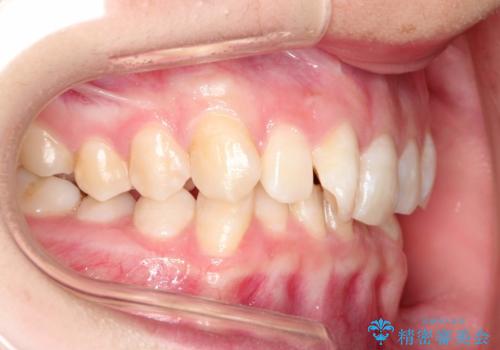

ハーフリンガル ワイヤー矯正による非抜歯・過蓋咬合の治療

- 非抜歯、大臼歯遠心移動による臼歯関係の是正・過蓋の改善をハーフリンガル・ワイヤー矯正にて計画した。

しかし、諸々の理由でマウスピース矯正をおこなえない場合、本例のようにワイヤーを用いて治療することも可能ですが、そもそも装置が歯につかないため、非常に大変な労力を費やすことになります。